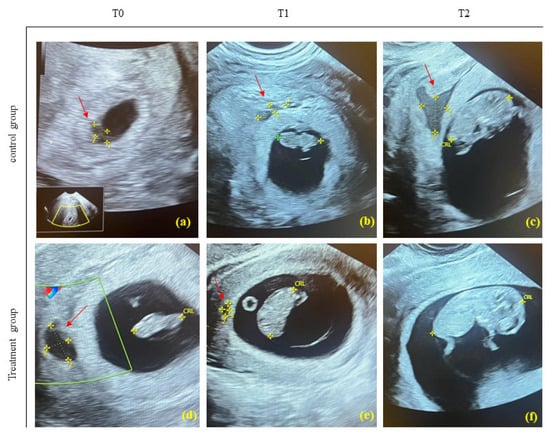

2.1. Sonographic Visualization of a Subchorionic Hematoma